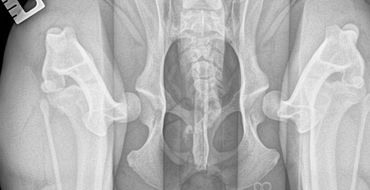

This technique requires 3 xrays views be taken while the dog is sedated.

The three views are

Often the distraction view shows greater laxity (looseness) in the hip than the hip extended view. This is because the hip extended view often masks hip laxity due to the position the socket is stretched into. This is why both views are required to be assessed with PennHIP scoring. The compression view allows the radiologist to assess the fit of the femoral head (ball) into the acetabulum (socket).